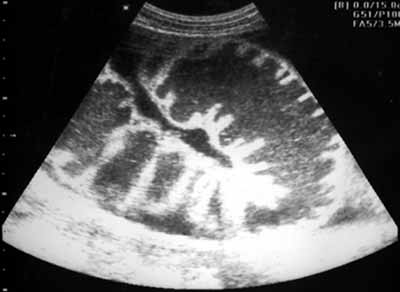

Рис. 1. Эхограмма больного с механической тонкокишечной непроходимостью - спаечный процесс на уровне проксимальных отделов подвздошной кишки. При продольном сканировании на уровне тощей кишки отмечается внутрипросветное депонирование жидкости, расширение просвета тонкой кишки, утолщение складок.